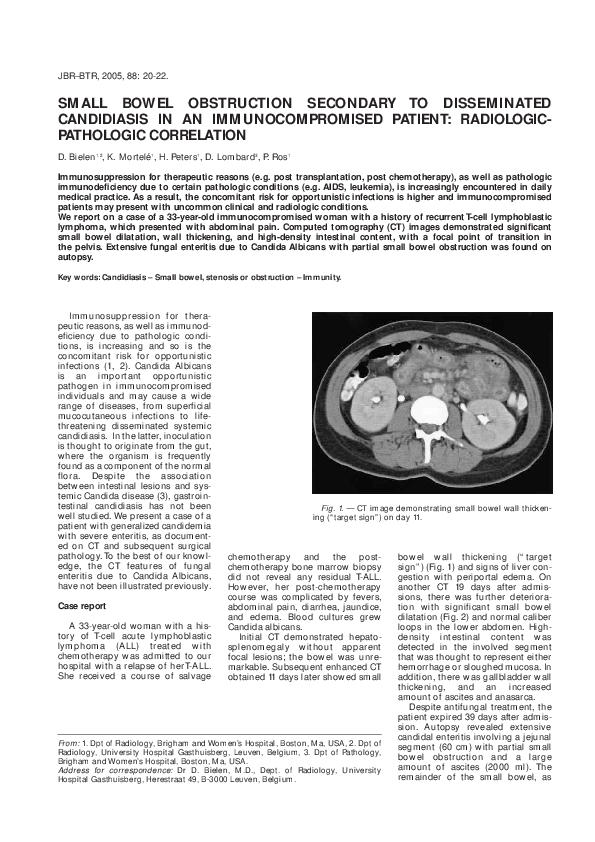

(PDF) Small bowel obstruction secondary to disseminated candidiasis in Candidiasis In Immunocompromised Patients candida albicans can cause mucosal candidiasis in these areas where they usually are present in an immunocompromised. invasive fungal disease (ifd) causes morbidity and mortality in immunocompromised hosts (ichs). in this review, we describe the mechanisms behind the pathogenesis and diagnosis of candida infections in such hosts. oral candidiasis can occur in immunocompetent or immunocompromised patients. Candidiasis In Immunocompromised Patients.